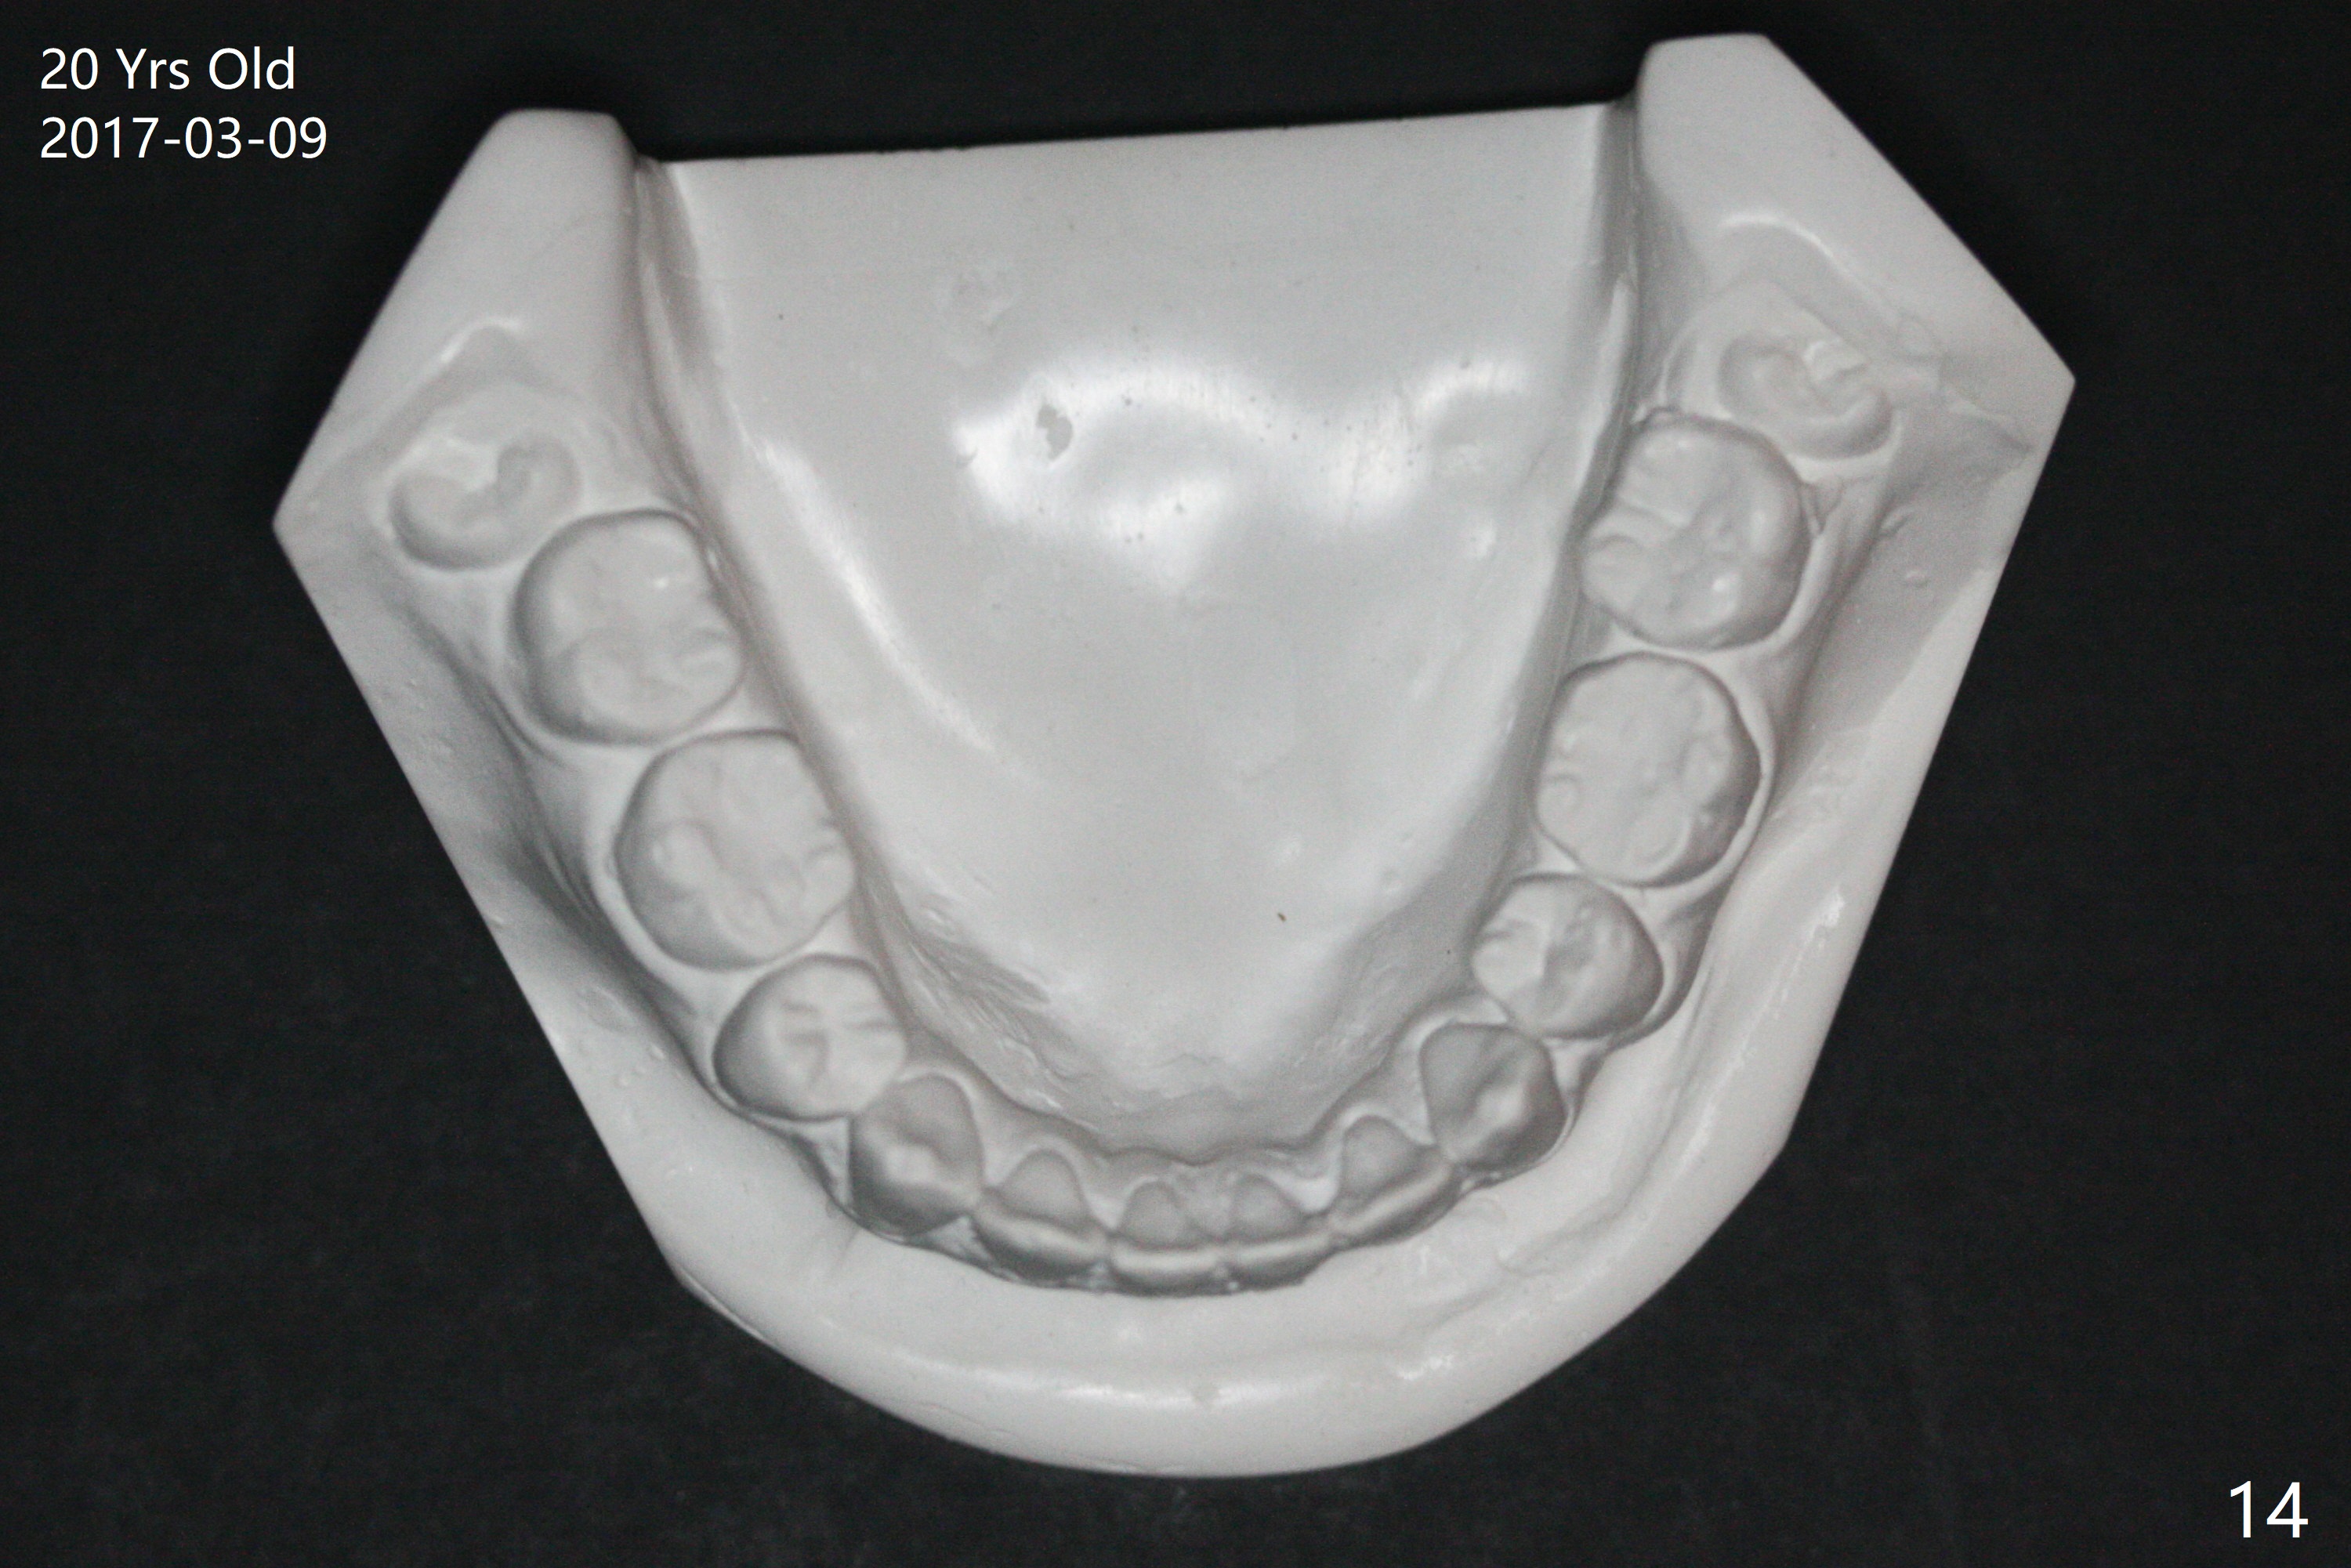

A 16-year-old man has severe crowding, but the open bite is ignored (Fig.1,4,7,10,13). The orthodontic treatment lasts 4 years 5 months, including failure to return for a period of time. The open bite seems to have been corrected (Fig.2, 5, 8, 11, 14). Suction down retainers are provided. In less than 2 years, the patient returns requesting remaking retainers. It appears that open bite relapses (Fig.3,6,9,12,15), as related to supraeruption of the lower 2nd molars (Fig.6,9 arrows). The latter is apparently associated with the erupting 3rd molars.